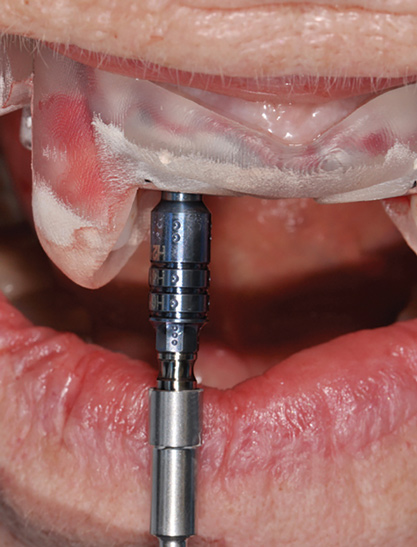

Fig 14. The printed static guide is used to precisely control preparation of osteotomy (Fig 14) and delivery of the implant through the guide (Fig 15).

Figure 14

Fig 15. The printed static guide is used to precisely control preparation of osteotomy (Fig 14) and delivery of the implant through the guide (Fig 15).

Figure 15

Digital Touchpoint 4: Surgical Guide Fabrication (and Transitional Restoration Components)

From the data and collaboration in steps 1 through 3, surgical guides can be fabricated for static surgery, and when indicated, prosthetic components, such as custom healing abutments, provisional crowns, or fixed partial dentures, can be produced for delivery at the time of surgery to guide soft-tissue healing. The static approach, better known as computer-guided surgery, refers to the use of tissue-tooth or soft- and hard-tissue-supported surgical templates. In essence, the virtual implant position planned from the CBCT, IOS, and face-in data sets is reproduced. The guide is produced with master cylinders (portals) through which the osteotomy preparation drills are introduced, and in full-guidance cases, the delivery of the implant is carried out (Figure 14 and Figure 15). Dynamic guided surgery or computer "navigation" traces the virtual implant position directly from CBCT data and employs motion tracking or real-time tracking technology to prepare the implant osteotomy. This makes it possible to determine the actual position of the surgical drill on the reconstructed 3D image provided by the CBCT. The surgeon is guided to the position that was planned preoperatively while he or she performs the surgical procedure. Examples of dynamic navigation systems are Navident (ClaroNav, claronav.com), X-Guide Dynamic 3D Navigation (X-Nav, x-navtech.com), Image Guided Implant (IGI) Dentistry System (Image Navigation, image-navigation.com), Inliant® (Navigate Surgical, navigatesurgical.com), and YOMI®, a robotic haptic guidance system (Neocis, neocis.com).